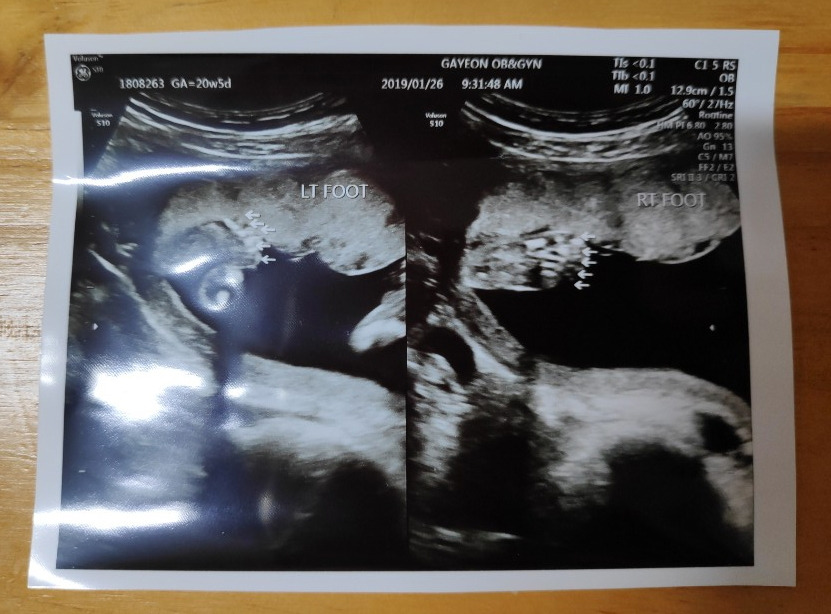

꼬톨이의 손과 발, 뇌, 장기 등이 정상적으로 자리 잡아가고 있는지를 보는 2차 정밀 초음파날!

초음파실에 들어가 하나하나 꼼꼼히 꼬톨이의 모습을 확인했다.

20분 정도 초음파를 본 것 같다. 손과 발 5개씩, 귀는 2개, 심장을 잘 뛰고 있는지.